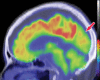

Neurodegenerative diseases are a devastating group of disorders that can be difficult to accurately diagnose. Although these disorders are difficult to manage owing to relatively limited treatment options, an early and correct diagnosis can help with managing symptoms and coping with the later stages of these disease processes. Both anatomic structural imaging and physiologic molecular imaging have evolved to a state in which these neurodegenerative processes can be identified relatively early with high accuracy. To determine the underlying disease, the radiologist should understand the different distributions and pathophysiologic processes involved. High-spatial-resolution MRI allows detection of subtle morphologic changes, as well as potential complications and alternate diagnoses, while molecular imaging allows visualization of altered function or abnormal increased or decreased concentration of disease-specific markers. These methodologies are complementary. Appropriate workup and interpretation of diagnostic studies require an integrated, multimodality, multidisciplinary approach. This article reviews the protocols and findings at MRI and nuclear medicine imaging, including with the use of flurodeoxyglucose, amyloid tracers, and dopaminergic transporter imaging (ioflupane). The pathophysiology of some of the major neurodegenerative processes and their clinical presentations are also reviewed; this information is critical to understand how these imaging modalities work, and it aids in the integration of clinical data to help synthesize a final diagnosis. Radiologists and nuclear medicine physicians aiming to include the evaluation of neurodegenerative diseases in their practice should be aware of and familiar with the multiple imaging modalities available and how using these modalities is essential in the multidisciplinary management of patients with neurodegenerative diseases.©RSNA, 2020.